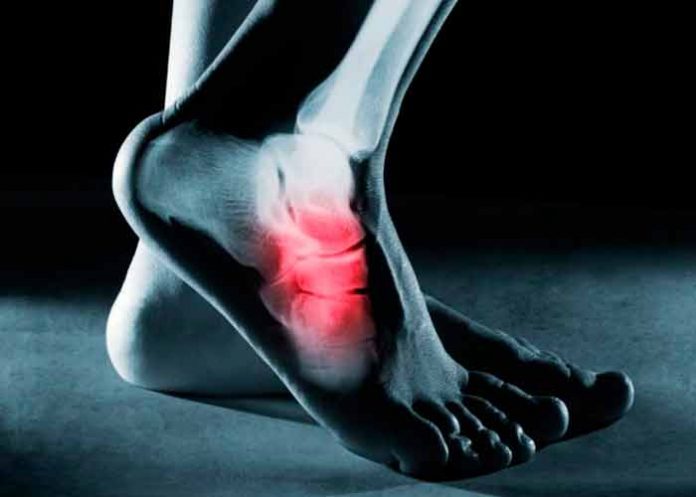

De acuerdo con la ortopedista brasileña Giuliano Mestriner, de la Clínica Fares, fascitis plantar es la inflamación de las plantas de los pies, más específicamente de la fascia plantar, que es el tejido fibroso que se extiende desde el talón a los dedos.

La principal manifestación es sentir dolor en los pies justo después de despertarte y pisar el suelo. Sin embargo, a medida que caminas, la incomodidad mejora.

"La fascia plantar se queda sin flexibilidad durante la noche, lo que genera dolor en la primera pisada del día, pero en la medida en que esa región es estimulada al caminar, se calienta y estira, y el dolor se desvanece", resalta el ortopedista Giuliano Mestriner.